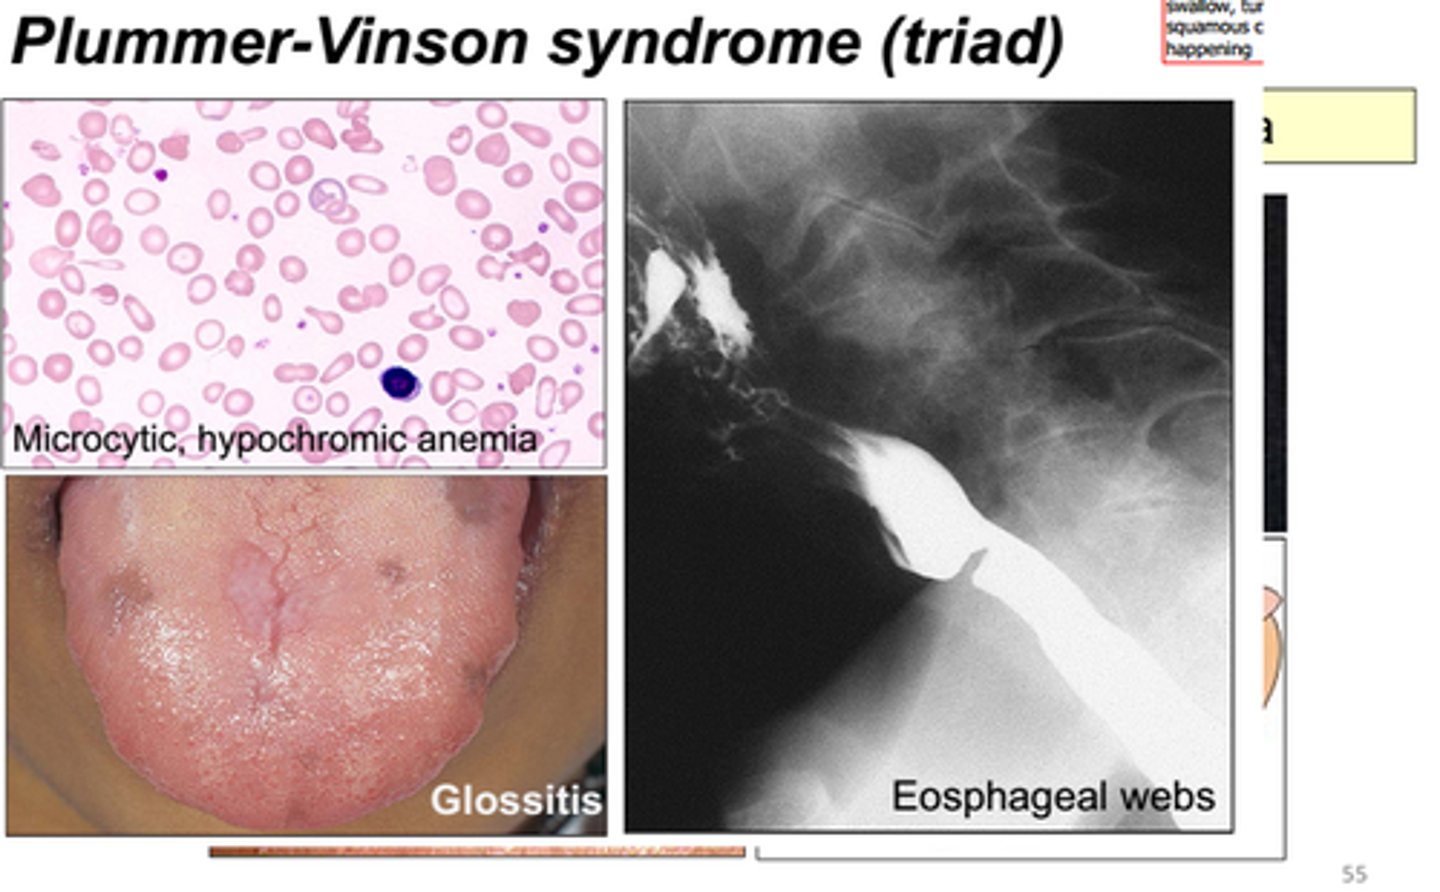

Dysphagia (esophageal webs), glossitis (beefy red tongue), iron deficiency anemia (spoon nails)

Plummer-Vinson syndrome

(may progress to esophageal squamous cell carcinoma)